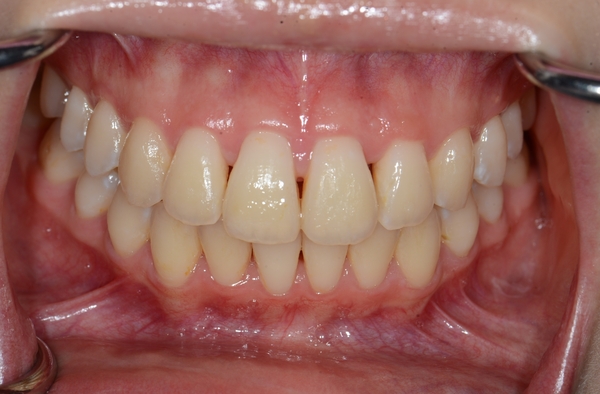

ガタガタとした歯並びや八重歯(叢生)CASE72